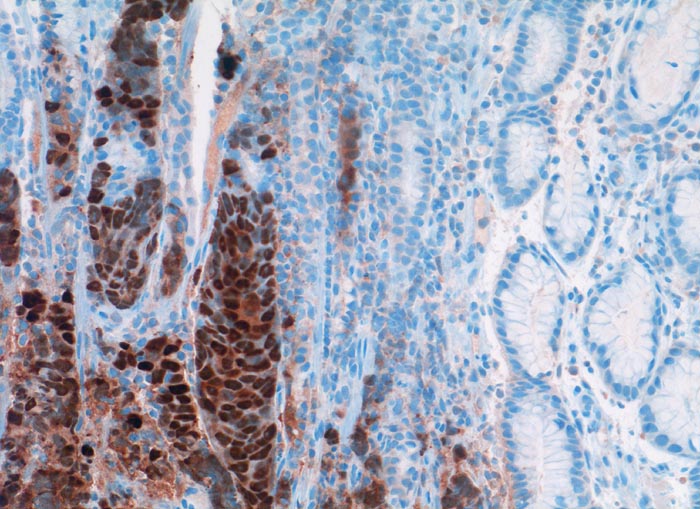

Die Tumorzellen füllen die Drüsenschläuche des Magens aus und verdrängen die orstständigen Zellen. Die Tumorzellkerne sind stark positiv für den Östrogenrezeptor.

Oestrogen Rezeptor